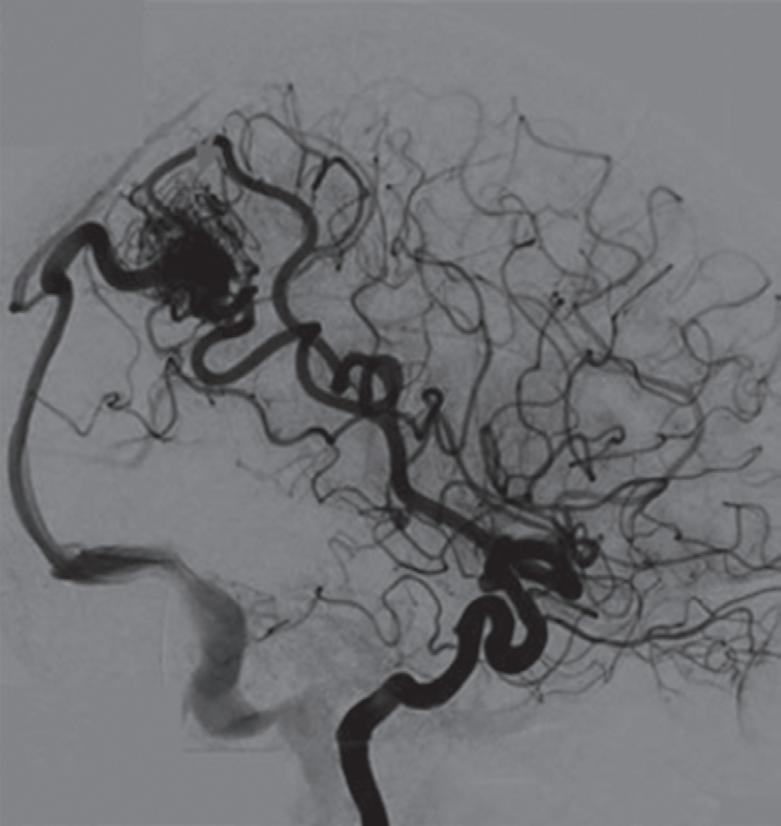

Com relação ao fluxo no interior do nidus, alguns autores classificam-nas em alto fluxo (Fig. 1-8) e baixo fluxo (Fig. 1-9). São consideradas de alto fluxo aquelas em que a opacificação após injeção de contraste ocorre apenas na malformação, em contrapartida, nas de baixo fluxo, ocorre opacificação da MAV e de outras artérias normais do mesmo território vascular. Exemplificando as lesões de alto fluxo temos as malformações arteriais, as malformações arteriovenosas e as fístulas arteriovenosas, enquanto as lesões de baixo fluxo são representadas pelas malformações venosas, linfáticas e capilares.25

Fig. 1-8. (a-c) RNM T1 com contraste, cortes sagital (a), coronal (b) e axial (c) demonstrando MAV não rota com nidus localizado no lobo occipital à esquerda (setas longas). (d) Arteriografia digital cerebral com injeção de contraste via carótida direita (AP) mostrando a contribuição da carótida direita na irrigação da MAV contralateral. (e,f) Com injeção de contraste via carótida esquerda, em Perfil e AP respectivamente, observa-se nidus compacto nutrido por ramos da artéria cerebral média à esquerda e a veia de drenagem precoce se dirigindo para o seio sagital superior. Projeções em AP (g) e em perfil (h) demonstrando a contribuição do sistema vertebrobasilar por meio de ramos distais da artéria cerebral posterior à esquerda e drenagem para os seios sagital superior e sigmoide à esquerda (setas curtas).